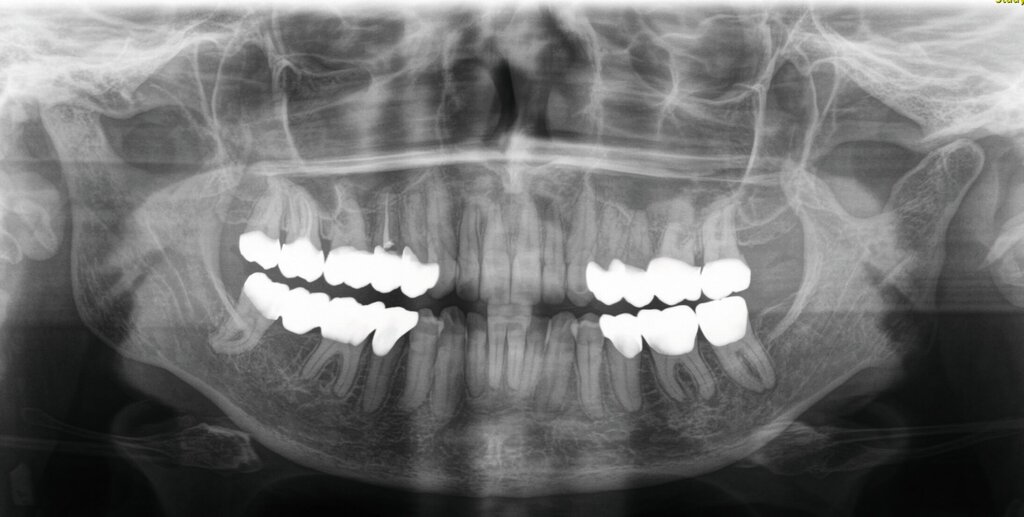

Im Rahmen der Konsultation der Mund-, Kiefer- und Gesichtschirurgie und der Kieferorthopädie erfolgte eine erneute radiologische Bildgebung (Abbildung 4). Die Patientin wurde im Anschluss beraten, dass eine Re-Osteotomie des ehemals frakturierten und nun in Fehlstellung verheilten Collumsegments links ihr Okklusionsproblem adäquat lösen könnte. Ebenso sei eine orthognathe Umstellungsosteotomie möglich. Nach ausführlicher Aufklärung entschied sich die Patientin allerdings gegen eine chirurgisch-kieferorthopädische und für eine rein prothetische Lösung. Die Patientin hatte derart Angst vor einem erneuten chirurgischen Eingriff, dass sie selbst die Aussicht auf eine längere und invasivere prothetische Behandlungsphase nicht abschreckte.